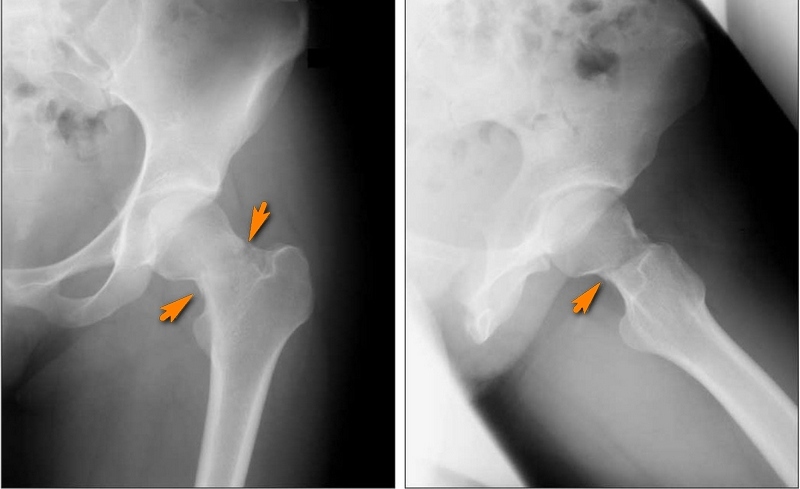

- рентгенография — определение типа перелома;

- МРТ бедра — выявление повреждений мягких тканей, сосудов, нервных окончаний и подсчет количества отломков.